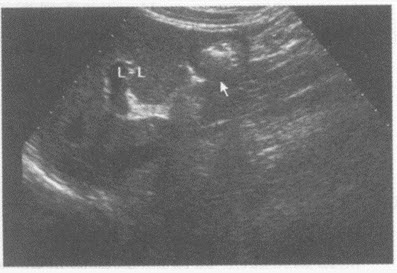

请回答下图是采用哪种肝脏扫查方式()A: 肝-胃纵切声像图B: 肝-下腔静脉纵切声像图C: 肝-腹主动脉纵切声像图D: 肝-胆囊纵切声像图

- A: 肝-胃纵切声像图

- B: 肝-下腔静脉纵切声像图

- C: 肝-腹主动脉纵切声像图

- D: 肝-胆囊纵切声像图